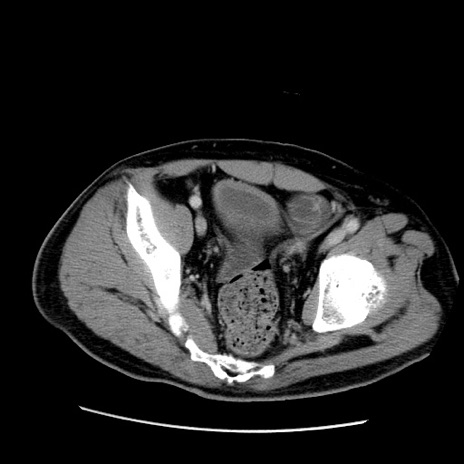

症例22(横断像)

【症例】50歳代男性

【主訴】腹痛

【現病歴】AVMからの被殻出血のため回復期リハ病棟入院中。 本日午後3時頃急に下腹部痛が出現した。

【既往歴】AVM、被殻出血、虫垂炎、高血圧

【身体所見】意識晴明、左半身不全麻痺、会話の理解は良好、36.5°C、腹部:膨隆、全体に板状硬、下腹部正中に圧痛点あり、反跳痛-、筋性防御不明、右下腹部にope scar

【データ】WBC 9400、CRP 0.06